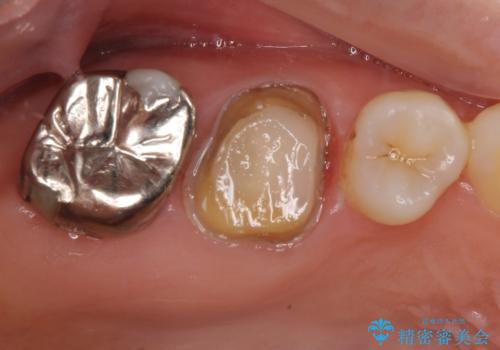

拡大鏡視野下で虫歯の除去を行い、オールセラミッククラウンに適した形に整えました。

型どりはシリコーン印象材にて精密印象をしています。

根管治療を施した歯は割れるリスクが上昇するため、詰め物(インレー)ではなく、被せ物(クラウン)にしなければなりません。